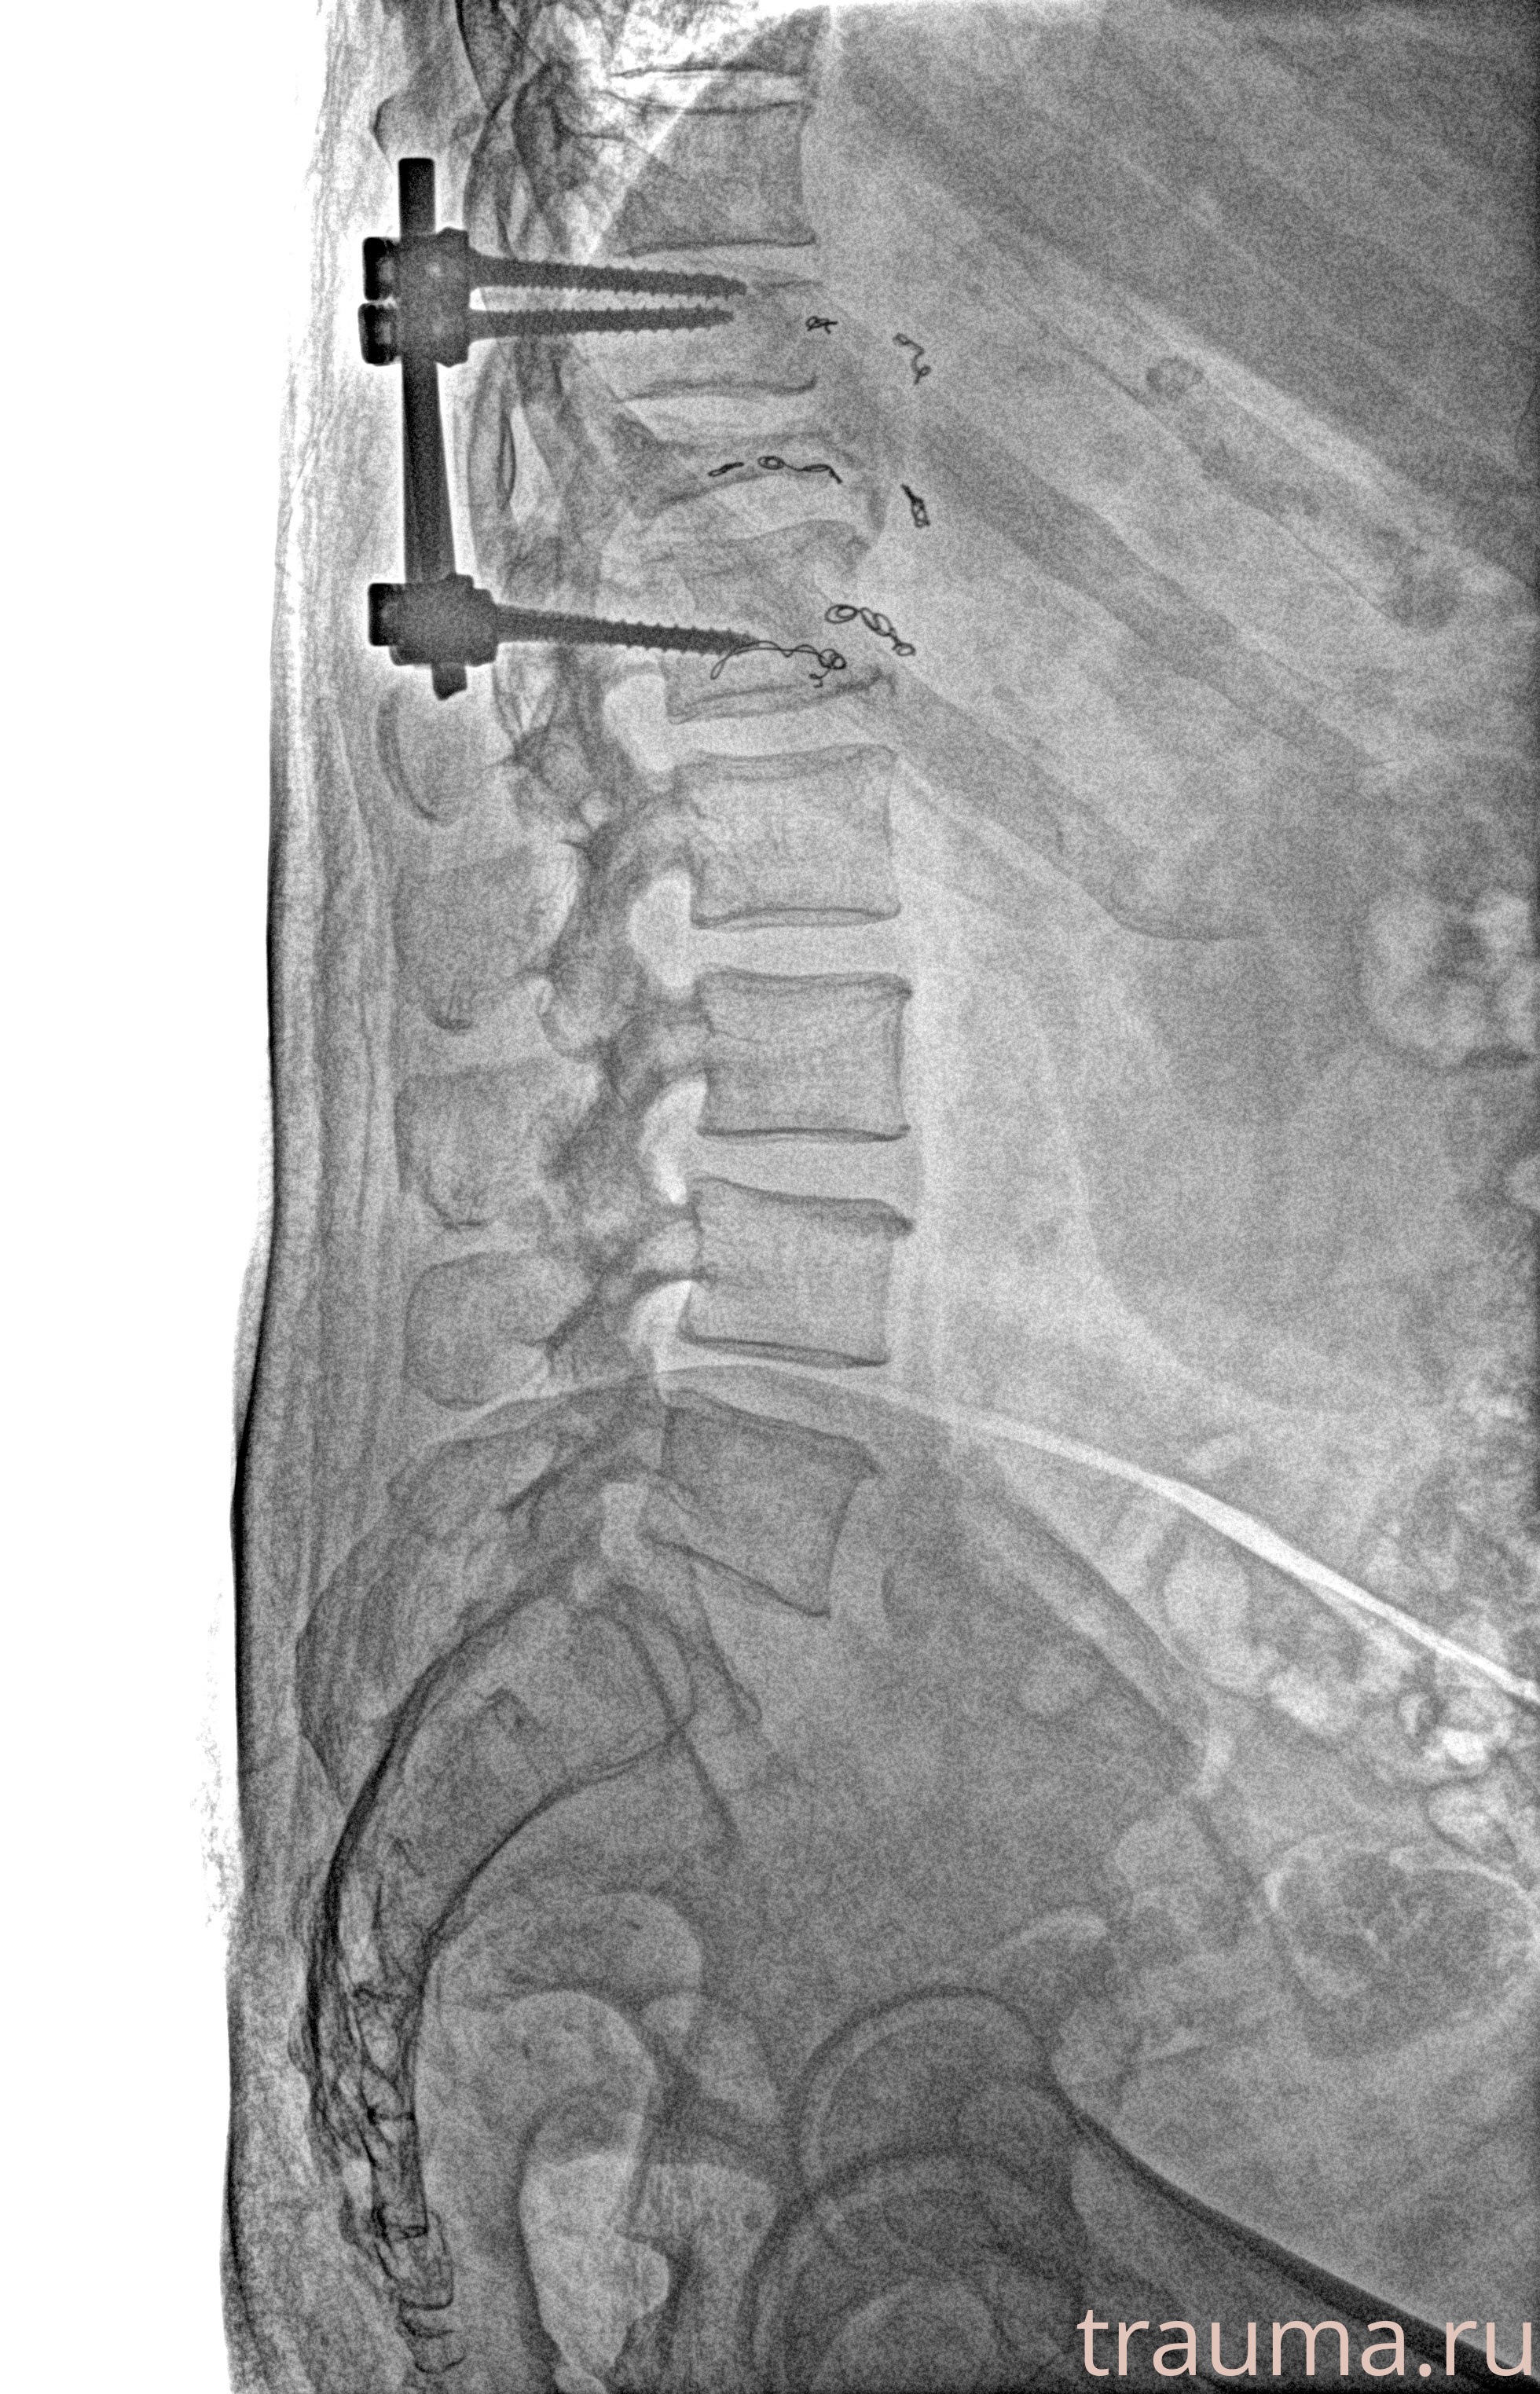

Рентгенограммы